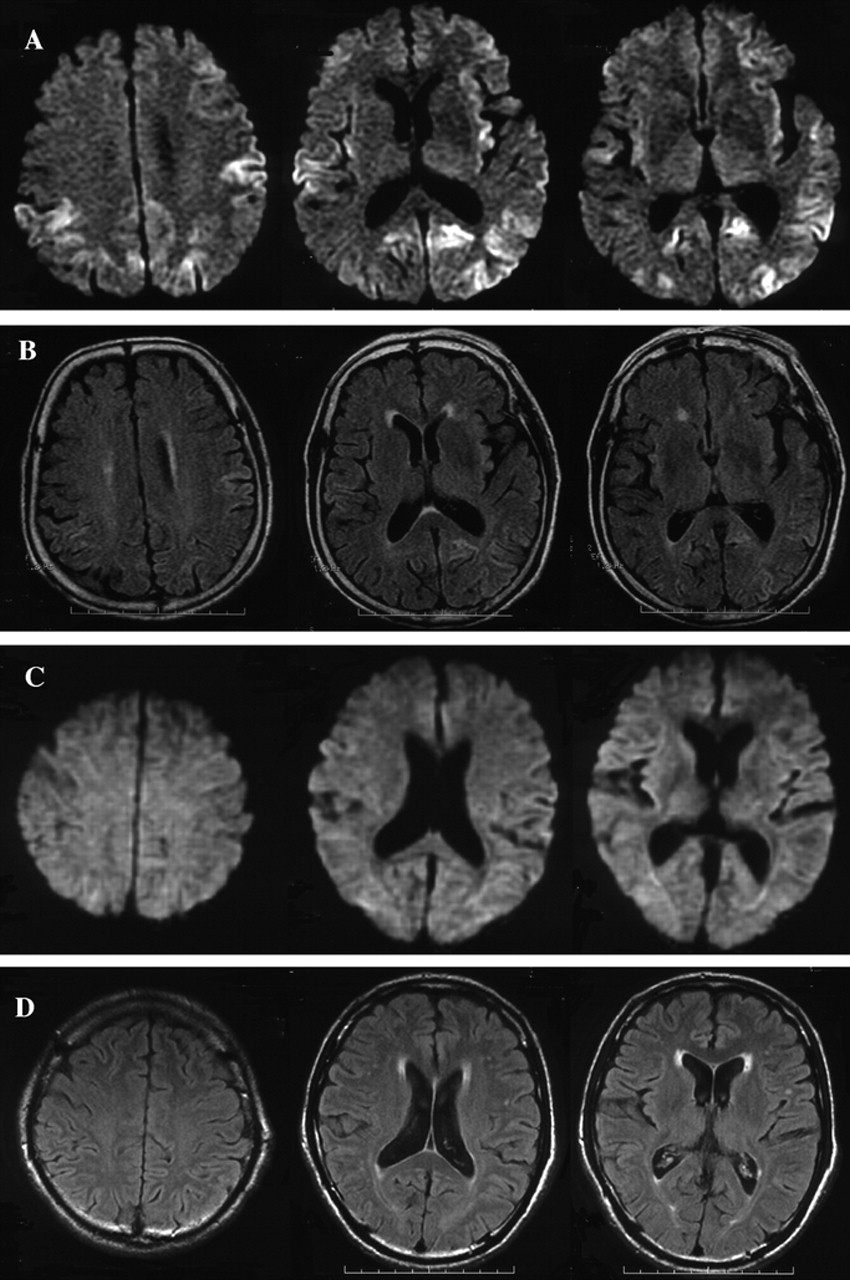

图1所示。大脑核磁共振在16个月后病人2 (A, B)和病人8在7个月后开始(C, D)。A和C是diffusion-weighted成像(驾车),和B和D是fluid-attenuated反转恢复(天赋)成像。在病人2中,酒后驾驶显示hyperintense信号双边额,顶叶、枕叶皮层(A),和天赋成像还显示轻微hyperintensity信号在大脑皮层驾车病变(B)。在病人8中,醉酒驾车和天赋大脑成像显示没有明显的异常信号(C, D)。

16个月后,MRI显示gyriform hyperintensity双边额叶,颞顶叶和枕叶皮层在diffusion-weighted成像(驾车)(图1一个)。那么激烈,皮质病变显示在小fluid-attenuated反转恢复成像(见图1 b)。脑电图,漫射放缓没有PSWCs被发现。CBF-SPECT使用99米Tc-ECD显示减少的CBF双边顶叶和颞皮层(图2一个)。脑脊液检查发现14-3-3蛋白水平增加(28 ng / mL(正常< 20 ng / mL))。尽管sCJD的临床标准20.并不满足,因为缺乏神经和脑电图异常,怀疑库贾氏症MRI和CSF的基础上发现。

神经系统检查4个月后开始显示含糊不清构音障碍,左侧上、下肢的笨拙,痴呆。EEG是正常的。14-3-3蛋白的CSF水平是模棱两可的。MRI显示gyriform hyperintensity双边额、颞、顶叶、枕叶皮质醉酒驾车。正的大脑显示弥漫性双边丘脑皮层代谢减退。库贾氏症被怀疑作为早期诊断。

患者1和2的平方毫米皮质出现迟发性的形式,慢慢进步的痴呆(表1)。PSWCs脑电图缺席在早期阶段(表2)。这些特性与之前报道的平方毫米皮质病例。3病人没有完成的临床标准sCJD因为缺乏临床症状。20.重要的是,大脑皮层hyperintensity信号驾车(见表2已报告),这为诊断sCJD是有用的,19日,22日,23日很容易使我们可能库贾氏症的诊断。基底节和丘脑在这些情况下没有hyperintensity核磁共振信号。CSF水平增加(见14-3-3蛋白支持诊断表2)。平方毫米皮质形式经常显示缓慢进行性痴呆没有其他神经系统异常,广告和痴呆与征收机构对鉴别诊断很重要。皮质hyperintensity信号在急性缺血性中风的醉酒驾车被发现,23单纯疱疹脑膜脑炎,22、23创伤后挫伤,22、23postictal变化,22和米拉(线粒体肌病、脑病、乳酸酸中毒和类似中风发作)24;然而,他们并没有观察到广告25或者和路易体痴呆。19我们建议以下为平方毫米皮质sCJD诊断标准:1)进行性痴呆,2)皮质hyperintensity信号在酒后驾驶,和3)脑脊液14-3-3蛋白质含量增加,排斥其他痴呆症,包括其他类型的朊病毒疾病。其他神经精神异常比痴呆或PSWCs脑电图不一定是必需的。

有趣的是,在病人与平方毫米(corticothalamic)形式(病人3)相结合,两平方毫米的神经影像学研究显示功能皮层和丘脑的形式,也就是说,hyperintense信号在醉酒驾车和丘脑皮层代谢减退摄影(见表2),与这个病人的病理结果一致。